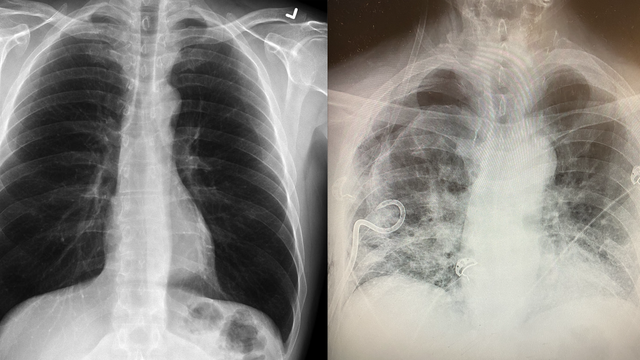

A surgeon in Texas revealed she’s seeing a pattern of lung scarring in some patients who have had COVID-19 that’s worse than what she sees in smokers’ lungs.